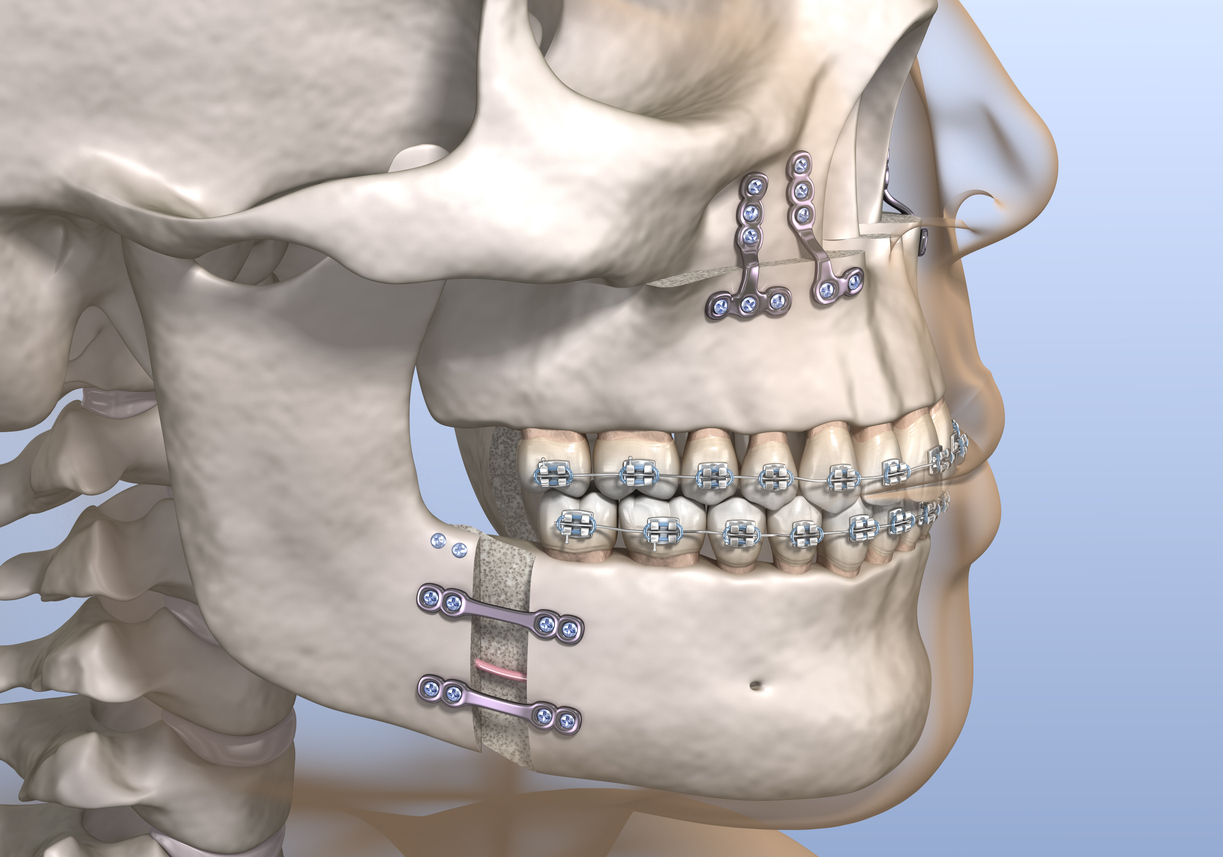

- Bimax (bimaxillary osteotomy) involves repositioning two jaws — the upper (maxilla) and lower (mandible) — to correct bite issues, facial imbalance, or airway problems.

Bimax involves repositioning both the maxilla (upper jaw) and mandible (lower jaw).

3. Custom Jaw Surgery vs Traditional Jaw Surgery

- Custom / 3D Bimax / Trimax (usually done at private clinics) : Uses virtual planning and custom titanium plates for perfect symmetry and aesthetic refinement.